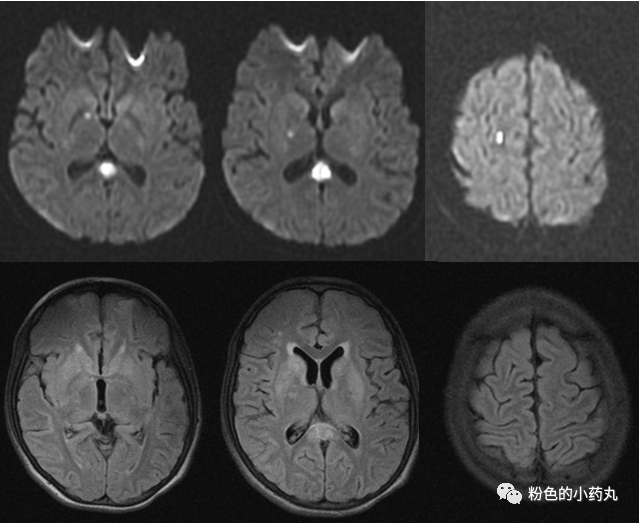

因遗传特征不同MRI通常呈异质性。一般来说,病灶分布对称。可分为三型: 基底节型、脑干型及白质型。

T2/FLAIR高信号,累及基底节中以壳核最多见,累及丘脑中以背侧丘脑内侧近第三脑室最多见。文献报道,双侧对称的壳核受累是必备的特征,尾状核、苍白球及丘脑可同时受累,但绝不会在壳核不受累的情况下单独出现。脑白质、皮层及小脑受累少见,病变范围较广可累及胼胝体和内囊。

T1常表现为低信号,但可见部分高信号,有一定强化。

DWI 的信号变化在时间分布上呈多样性,急性期DWI 病变可见弥散受限。

图 病例1